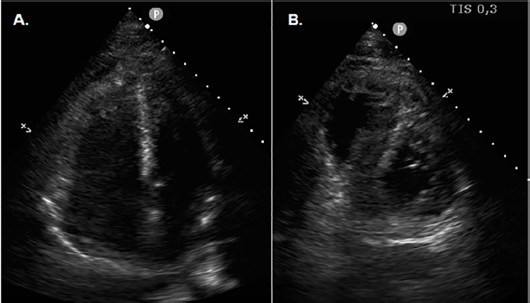

Se presenta el caso de un paciente masculino de 39 años, sin factores de riesgo ni antecedentes cardiovasculares, que como otros antecedentes refiere haberse sometido a una cirugía de tendón de Aquiles 45 días previos a la consulta. Concurre al Servicio de Urgencias por haber presentado en su domicilio un episodio de disnea súbita asociado a síncope sin pródromos con traumatismo craneoencefálico (TEC) Durante su estadía en Guardia presenta nuevo episodio sincopal. Se realiza un ecocardiograma transtorácico (ETT) Doppler (Figura 1) con evidencia de dilatación de cavidades derechas; por lo que, asociado al antecedente reciente de cirugía traumatológica, se sospecha TEP. Rápidamente evoluciona con PCR, por lo que se realizan maniobras de reanimación cardiopulmonar avanzadas y se decide, debido a antecedente de TEC, instaurar tratamiento percutáneo con tromboaspiración y trombolíticos locales. El paciente evoluciona con inestabilidad hemodinámica por lo que, tras descartar hemorragia intracraneal con tomografía, se administran trombolíticos sistémicos, a pesar de lo cual el paciente persiste con shock refractario a dosis máximas de drogas vasoactivas. Se establece contacto con Centro de Alta Complejidad y se activa el equipo de ECMO móvil. El paciente es asistido con ECMO venoarterial en el centro de origen una vez corregida la coagulopatía y posteriormente se traslada al Centro de Alta Complejidad. El paciente ingresa inestable hemodinámicamente, en asistencia ventricular y respiratoria, con requerimiento de dosis máximas de noradrenalina, vasopresina y milrinona; presenta en laboratorio injuria renal y hepática agudas, acidosis metabólica con hiperlactacidemia y coagulopatía marcada. Los valores de troponina T ultrasensible y de NT-proBNP al ingreso son 6700 ng/L y 480 pg./ mL respectivamente. El electrocardiograma (Figura 2) evidencia taquicardia sinusal y la radiografía de tórax, cardiomegalia y signos francos de redistribución de flujo bilateral. Durante las primeras 24 horas el paciente persiste con shock mixto (interpretado como cardiogénico y vasopléjico) con requerimiento de drogas vasoactivas, falla multiorgánica y coagulopatía marcada; se establecen cuidados postparo, sostén hemodinámico, corrección del medio interno, bajo asistencia ventricular. Tras corregir valores críticos de fibrinógeno se instaura tratamiento anticoagulante con heparina sódica en infusión continua, ajustado a valores de anti Factor Xa. Evoluciona con descenso de drogas vasoactivas, mejoría de la función ventricular derecha por ETT por lo que a las 72 horas se realiza prueba de weaning de la ECMO que resulta favorable y se decide retirar asistencia circulatoria sin complicaciones. El paciente permanece bajo intubación orotraqueal, con respuesta neurológica intacta y buen volumen urinario con respuesta a diuréticos endovenosos (a pesar de valores séricos de creatinina en ascenso con pico de 10 mg/dL, pero sin requerimiento de hemodiálisis); por lo que al séptimo día de su ingreso la extubación es exitosa. Realiza rehabilitación kinésica motora y respiratoria exhaustiva posterior; se descarta síndrome antifosfolipídico y otras trombofilias; realiza balance negativo con diuresis forzada a expensas de furosemida con buena respuesta, por lo que retorna a su centro de origen para continuar con la rehabilitación en sala general, con un ECG con evidencia de aumento de los voltajes (Figura 2) y un ETT con función biventricular completamente normalizada.